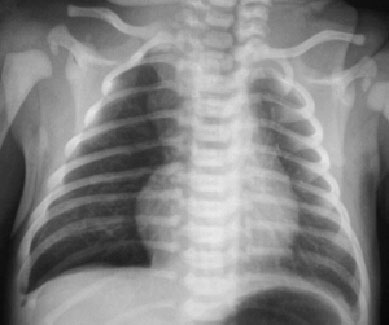

SIGNO DEL HEMITÓRAX HIPERCLARO

Signo de neumotórax en la radiografía de tórax en supino. Aunque ha sido descrito en el neumotórax neonatal, también puede verse en adultos. Por supuesto, hay que descartar otras causas de hiperclaridad, especialmente la rotación de la proyección.

El signo es más útil cuando se asocia a una mejor definición del borde mediastínico de ese lado como consecuencia del contacto del aire libre con dicho borde (signo del margen nítido).

En la imagen vemos que el hemitórax derecho es menos denso que el izquierdo por la presencia de neumotórax. Se aprecia, además el margen cardíaco derecho nítido.